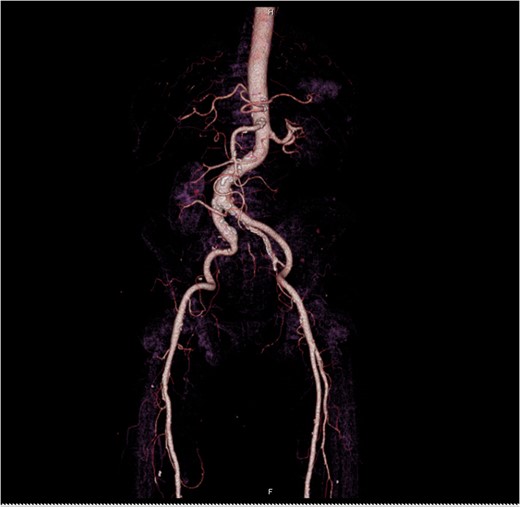

At Emergency department, physical exam showed hypotension blood pressure 70/50 mmHg and per rectal exam showed blood clot with enlarged prostate. After resuscitation until stable vital sign, he was sent for colonoscopy but cannot be evaluated due to a lot of blood clots in the rectum. He was admitted for observation and we planned to repeat colonoscopy again following day because he was stable and bleeding was stopped. Following day after admitting, he had massive lower gastrointestinal bleeding again fresh blood ~1000 ml from his anus. His blood pressure was lower 80/50 mmHg. After stabilization, we planned to send the patient to angiogram for embolization. But the patient had a problem vascular access site and then send to computed tomography angiography (CTA) for evaluate access site. We found 3 cm aneurysm of right internal iliac artery with partial thrombus and attached to rectosigmoid colon with leakage of contrast into sigmoid lumen (Figs 1–2). He was sent to operating room during transferring we gave blood transfusion and then emergency explore laparotomy was performed, the operation performed by partial aneurysmectomy, ligated right internal iliac, wedge resection rectum wall and temporary abdominal closure with swab packing due to bowel distension and abdominal pressure was high. The operative time was around 3 hours and blood loss 6000 cc. He was sent to operating room for change swab packing on Day 3 and permanent abdominal closure on Day 5. During postoperative period, he developed acute cholecystitis and underwent open cholecystectomy. After admit for 1 month, he was discharged with fully recovery.

This case was send to the operating room after diagnosis right internal ilio-rectal fistula for emergency exploration with laparotomy because the patient’s active bleeding and vital signs were not stable preventing adequate preparation time for intervention or stent graft in hospital. We decided to ligate right internal iliac artery, wedge resection rectum with suture repair because this is a simple operation and can save patient’s life. Other options could be done by endovascular therapy or embolic coiling if we had time to prepare and the patient was already stabilized in this hospital.